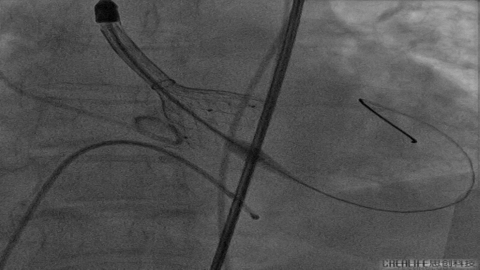

VenusA26号完全释放

最后一枪造影

超声显示人工瓣膜工作良好,微量瓣周漏,术后一周顺利出院,术后随访无并发症,恢复良好。